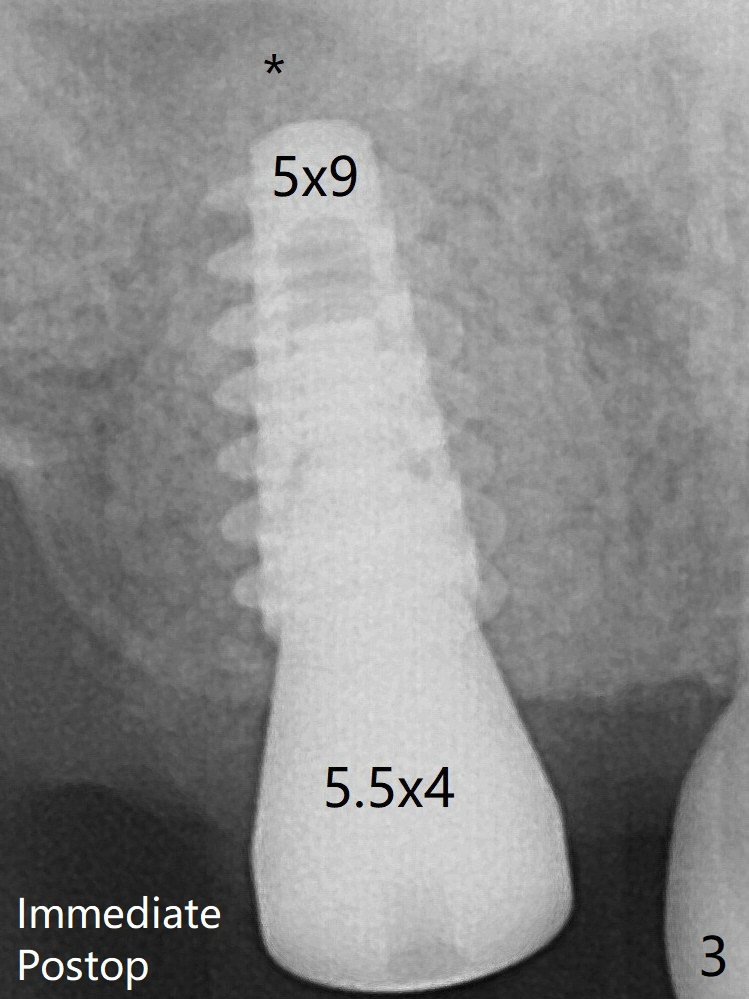

The implant threads are subcrestal 5 months postop (Fig.5).